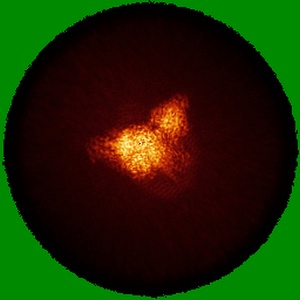

CryoEM structure of mu-opioid receptor - Gi protein complex bound to lofentanil (LFT)

Single-particle3.2 Å

Sample: mu-opioid receptor - Gi protein complex bound to lofentanil (LFT)